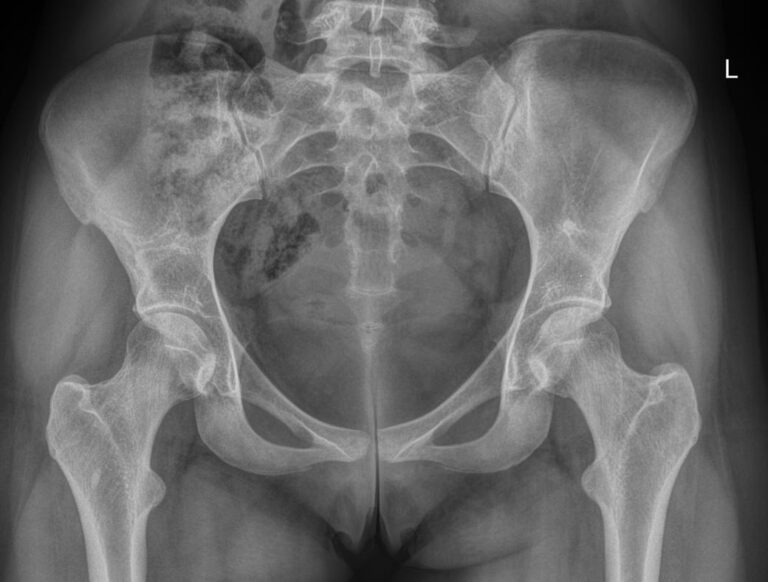

Рентгеновская методика основана на способности ионизирующего излучения проходить сквозь ткани. Кости, как самые плотные образования тела, поглощают наибольшее количество излучения и на негативном снимке визуализируются самыми светлыми. Все изменения ― от трещин до опухолей ― видны четко. Еще один плюс в том, что на рентгенограмме видны сразу все расположенные здесь костные структуры: нижние поясничные позвонки, крестец и копчик, а также тазовые кости ― лонная, седалищная и подвздошная.

Что показывает рентген костей таза

• Костную структуру: есть ли участки разрежения;

• Состояние крестцово-подвздошных сочленений ― в норме должны быть симметричны;

• Переломы, в том числе зажившие;

• Если есть новообразования или метастазы ― указывают их местоположение и размеры.